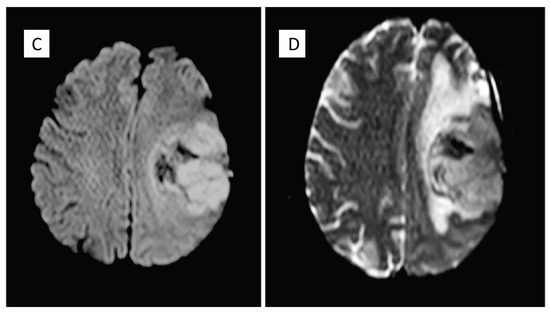

| Years | Symptoms | Diagnosis | Treatment |

|---|---|---|---|

| 2010 | Headache, speech difficulties and hypersomnia | Neoplastic lesion in the left frontparietal area compatible with papillary meningioma | Surgical removal and radiotherapy adjuvant treatment |

| 2015 | Headache | Recurrence of PM | Neurosurgical removal |

| 2020 | Headache, sleep disturbances and functional symptoms | Recurrence of PM | Tumour excision |